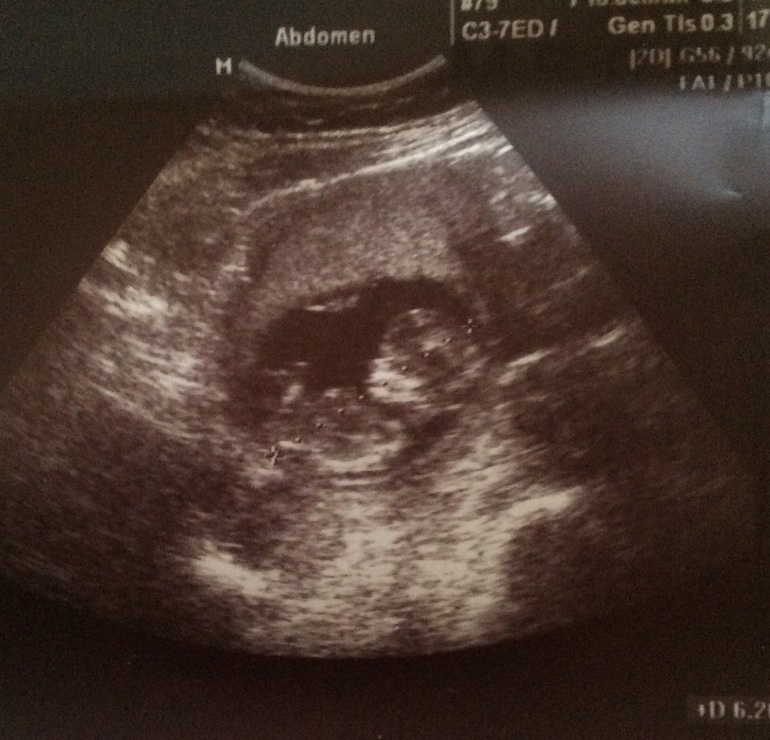

Переделала узи

УЗИ, КТГ, доплерчувствовала я что в пятницу нас плохо померили

Сказали что мы 50 мм

Не думала что все помериют))) и на кого торчок похож между ног?)

не полагайтесь на сердцебиение, а так же на торчок)))) врач сказала что это может быть как и клитор, так и писюн))) ждем дальше